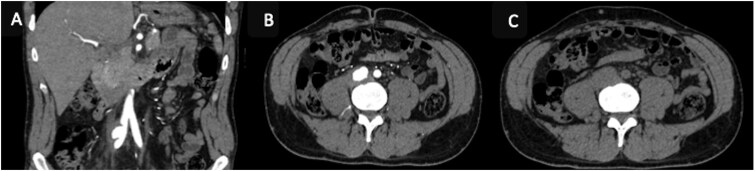

相对罕见的髂总动脉动脉瘤是血管的异常扩张,在罕见的情况下,可能会因破裂而复杂化,破裂可能被周围的结构所包含。影像学,特别是CT血管造影,在诊断中起着关键作用。我们报告一例包含破裂的髂总动脉瘤负责肾积水,髂总静脉阻塞,和邻近椎体的溶解。

Relatively rare aneurysms of the common iliac artery are abnormal dilatations of the vessel, which can be complicated by a rupture that, in rarer cases, may be contained by surrounding structures. Imaging, particularly CT angiography, plays a key role in diagnosis. We report a case of a contained rupture of the common iliac artery aneurysms responsible for hydronephrosis, obstruction of the common iliac vein, and lysis of the adjacent vertebra.